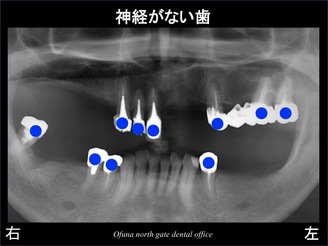

神経がない歯は以下のレントゲンの青丸になります。

神経のない歯が非常に多いのが分かります。

いつも説明していますが、神経のない歯は脆く さまざまなトラブルが起こりやすい 状態です。